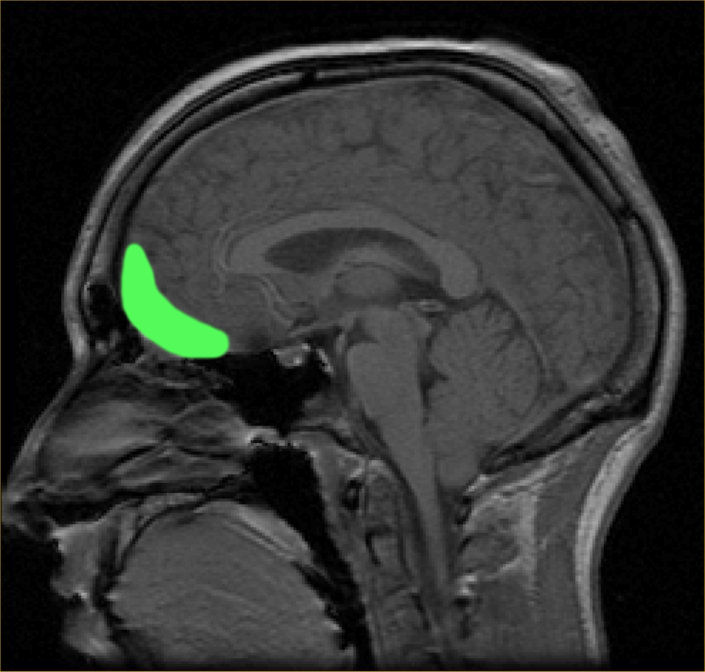

Figure 1: A sagittal MRI view of the human orbitofrontal cortex.

Researchers at the University of California, San Francisco led by Dr. Prasad Shirvalkar sought to identify biomarkers of pain states in the frontal brain regions of patients with chronic, refractory neuropathic pain. The researchers set up a deep-brain stimulation clinical trial for four such patients, surgically administering intracranial electrode and neurostimulator implants into their anterior cingulate and orbitofrontal cortices (ACC & OFC), two regions believed to be involved in the affective and cognitive processing of pain. Ambulatory neural recordings were captured for six months, with subjects’ pain score reports being cross-referenced with the recordings to longitudinally map fluctuations in pain states. Finally, the pain states were decoded, assigning ‘high’ and ‘low’ intensity labels to distinct signals in the recordings. This aimed to determine whether the cortical signatures were indeed predictive biomarkers of chronic pain.

Researchers found that subjects’ pain reports correlated with local field potential signaling detected in the neural recordings, with clear distinctions between the firing patterns of acute and chronic pain. Chronic pain was primarily decodable in the OFC, with the decoding reflecting sustained changes in neural power over larger time intervals, while the ACC supported more frequent and transient changes in power akin to that of acute pain. This suggests that chronic pain particularly depends on signaling activity in the OFC, underscoring its potential status as a biomarker of associated pain states. These findings represent the first time in vivo neural recordings of chronic pain signals in the human brain have been captured – a significant milestone in the path to developing therapeutics that may predict and disrupt prolonged signaling. Follow-up studies will likely test the same conclusions in significantly larger patient populations and explore firing patterns in other cortical regions.